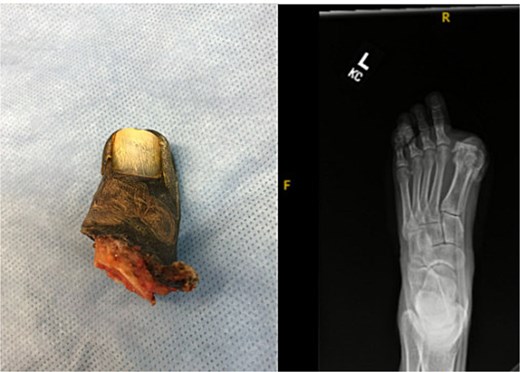

A 44-year-old active woman, with a body mass index of 19.7, presented with symptomatic left hallux rigidus. Her past medical history included only celiac disease; she had no history of smoking, diabetes, peripheral vascular disease, or other conventional vascular risk factors. Her sole medication was spironolactone. She underwent standard first MTP arthrodesis with articular surface preparation, demineralized bone matrix, and fixation using two headless compression screws (Fig. 1). A tourniquet was applied just above the ankle; however, the exact duration was not available because the procedure was performed at an outside hospital. She received perioperative cefazolin prophylaxis.

Postoperative radiograph showing first metatarsophalangeal joint arthrodesis with two headless compression screws.